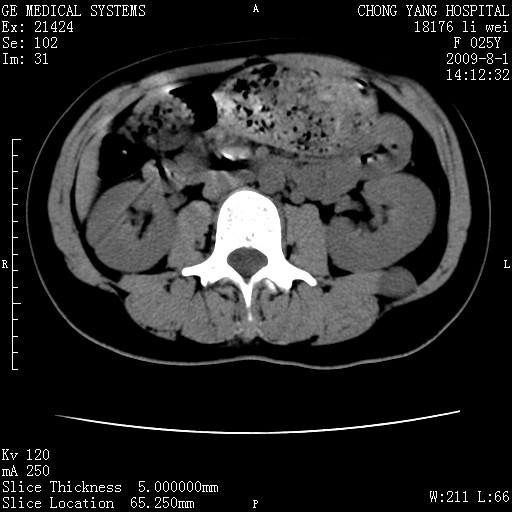

以下是引用pujunzhi在2009-8-1 20:23:00的发言:[br]胸椎旁及背部肌间良性病变,范围广,边界清,沿肌间生长,考虑淋巴管瘤、血管瘤,建议增强扫描。

以下是引用拾荒者在2009-12-30 21:45:00的发言:[br]ct21383:神经纤维瘤病( nf) [br] [br] 神经纤维瘤病。四肢都有,影响美观,四肢上的手术了。[br] [br] [br]谢谢!